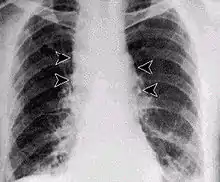

Inhalation anthrax usually develops within a week after exposure, but may take up to 2 months. During the first few days of illness, most people have fever, chills, and fatigue. These symptoms may be accompanied by cough, shortness of breath, chest pain, and nausea or vomiting, making inhalation anthrax difficult to distinguish from influenza and community-acquired pneumonia. This is often described as the prodromal period.[20]

Over the next day or so, shortness of breath, cough, and chest pain become more common, and complaints not involving the chest such as nausea, vomiting, altered mental status, sweats, and headache develop in one-third or more of people. Upper respiratory tract symptoms occur in only a quarter of people, and muscle pains are rare. Altered mental status or shortness of breath generally brings people to healthcare and marks the fulminant phase of illness.

It infects the lymph nodes in the chest first, rather than the lungs themselves, a condition called hemorrhagic mediastinitis, causing bloody fluid to accumulate in the chest cavity, therefore causing shortness of breath. The second (pneumonia) stage occurs when the infection spreads from the lymph nodes to the lungs. Symptoms of the second stage develop suddenly after hours or days after the first stage. Symptoms include high fever, extreme shortness of breath, shock, and rapid death within 48 hours in fatal cases.[21]